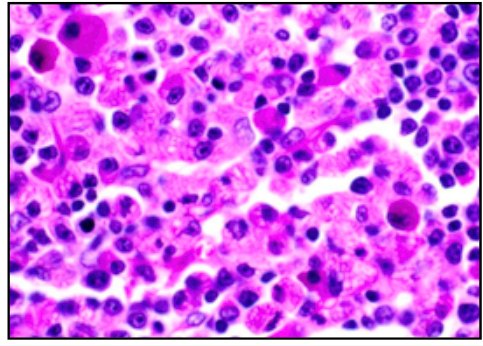

ROMANOVSKY/LEISHMANN’S (BLOOD FILMS)

• Chromatn/nuclei and neutrophil granules (PURPLE)

• eryhtrocytes/eosin granules (RED/PINK)

• lymphocyte/monocyte plasma (PALE BLUE)

• basophil granules (DARK BLUE/PURPLE)